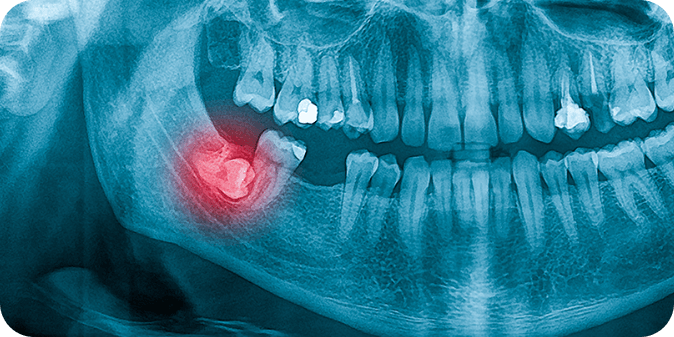

Due to their late emergence compared to other teeth, wisdom teeth often do not have enough space on the jaw to grow. In such cases, the wisdom tooth becomes impacted, and may grow

- At an angle towards the next tooth

- Towards the back of the mouth, or

- Along the jawbone at a right angle.

At other times, it may not break through the gums at all. These complications can sometimes cause painful symptoms.